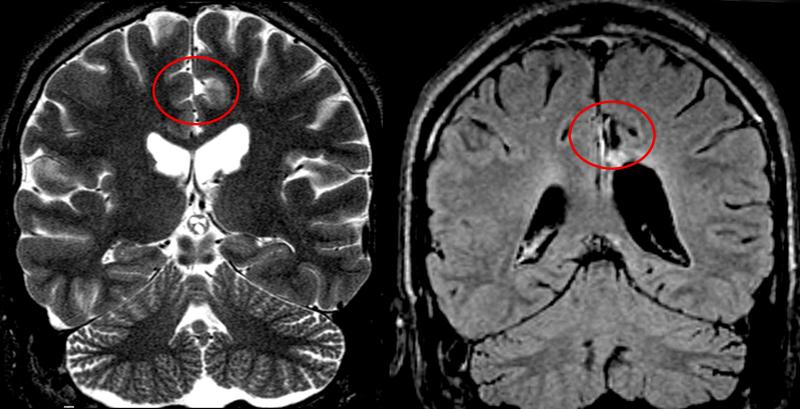

Die Epilepsieform FCD galt bislang als relativ schlecht operabel, da sich der krampfauslösende Hirnbereich schwer von gesundem Gewebe abgrenzen lässt. Doch die Weiterentwicklung bildgebender Verfahren wie der Magnetresonanztomografie, ergänzt durch hochauflösende Messungen der Hirnaktivität erlauben heute eine bessere Lokalisierung der Anfallsherde, die der Operateur dann präzise entfernt. Mikrochirurgische Techniken reduzieren nicht nur das Risiko operativer Komplikationen sondern minimieren auch das entfernte Gehirngewebe, so dass kognitive Leistungen des Gehirns bewahrt werden können.